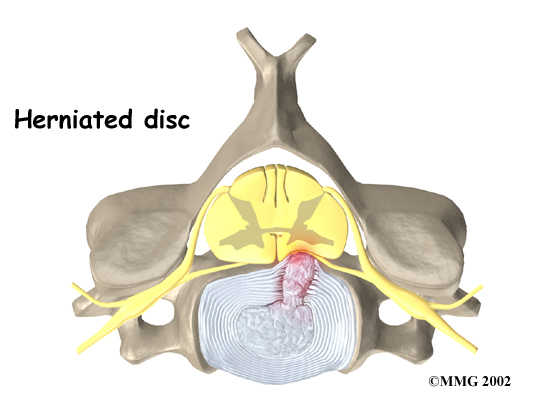

Disc herniation

Spinal stenosis can occur when a disc in the neck herniates. Normally, the shock-absorbing disc is able to handle the downward pressure of gravity and the strain from daily activities. However, if the pressure on the disc is too strong, such as from a blow to the head or neck, the nucleus inside the disc may rupture through the outer annulus and squeeze out of the disc. This is called a disc herniation. If an intervertebral disc herniates straight backward, it can press against the spinal cord and cause symptoms of spinal stenosis.

Neck Herniates

The changes that happen with degeneration and disc herniation can choke off the blood supply that goes to the spinal cord. The sections of the spinal cord that don't get blood have less oxygen and don't function normally, leading to symptoms of myelopathy.